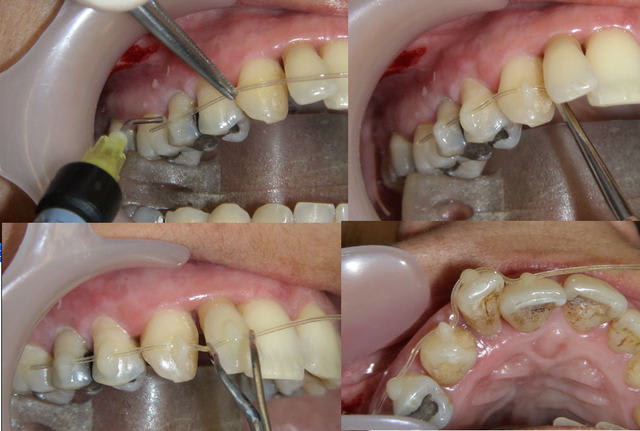

C'était ce matin, j'en ai profité pour faire ces photos à votre intention.

Des questions sur la procédure ?

Daniel